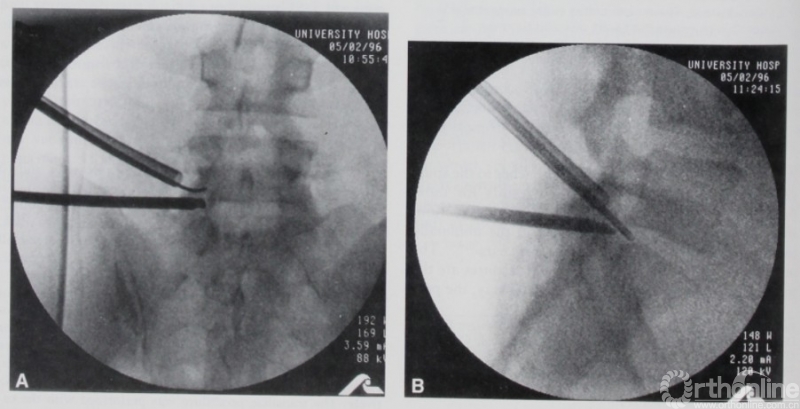

随着内镜光源和放大技术的进步,1996年,来自意大利的De Antoni DJ[15]首次描述了一种使用关节镜系统和器械施行的脊柱后方单侧双通道脊柱内镜技术,称之为“经椎板腰椎硬膜外内镜(translaminar lumbar epidural endoscopy)”技术。用以进行突出间盘摘除:患者采取侧卧位,工作通道切口位于目标节段体表垂直投影点,视线通道体表切口则根据非优势手的习惯位置选取。

这一技术可以视为现阶段单侧双通道脊柱内镜的前身。DE Antoni总结了一系列技术优点,如:易于处理L5-S1节段,可视化效果较好且对神经根扰动少,单一切口即可进行多节段处理,认为这一术式对过去椎旁脊柱内镜进行有效补充,提高微创技术的手术效果并扩大其手术指征。这与现阶段我们对脊柱双通道内镜优势的看法一致,但很遗憾,这一技术文献当时发表后并未引起广泛关注。

图4. 1997年Osman使用的单侧双通道脊柱内镜技术。引自Osman SG, Marsolais EB. Endoscopic transiliac approach to L5-S1 disc and foramen. A cadaver study. Spine (Phila Pa 1976) 1997;22(11):1259-1263.

15. De Antoni DJ, Claro ML, Poehling GG, Hughes SS. Translaminar lumbar epidural endoscopy: anatomy, technique, and indications. Arthroscopy 1996; 12(3):330-334.